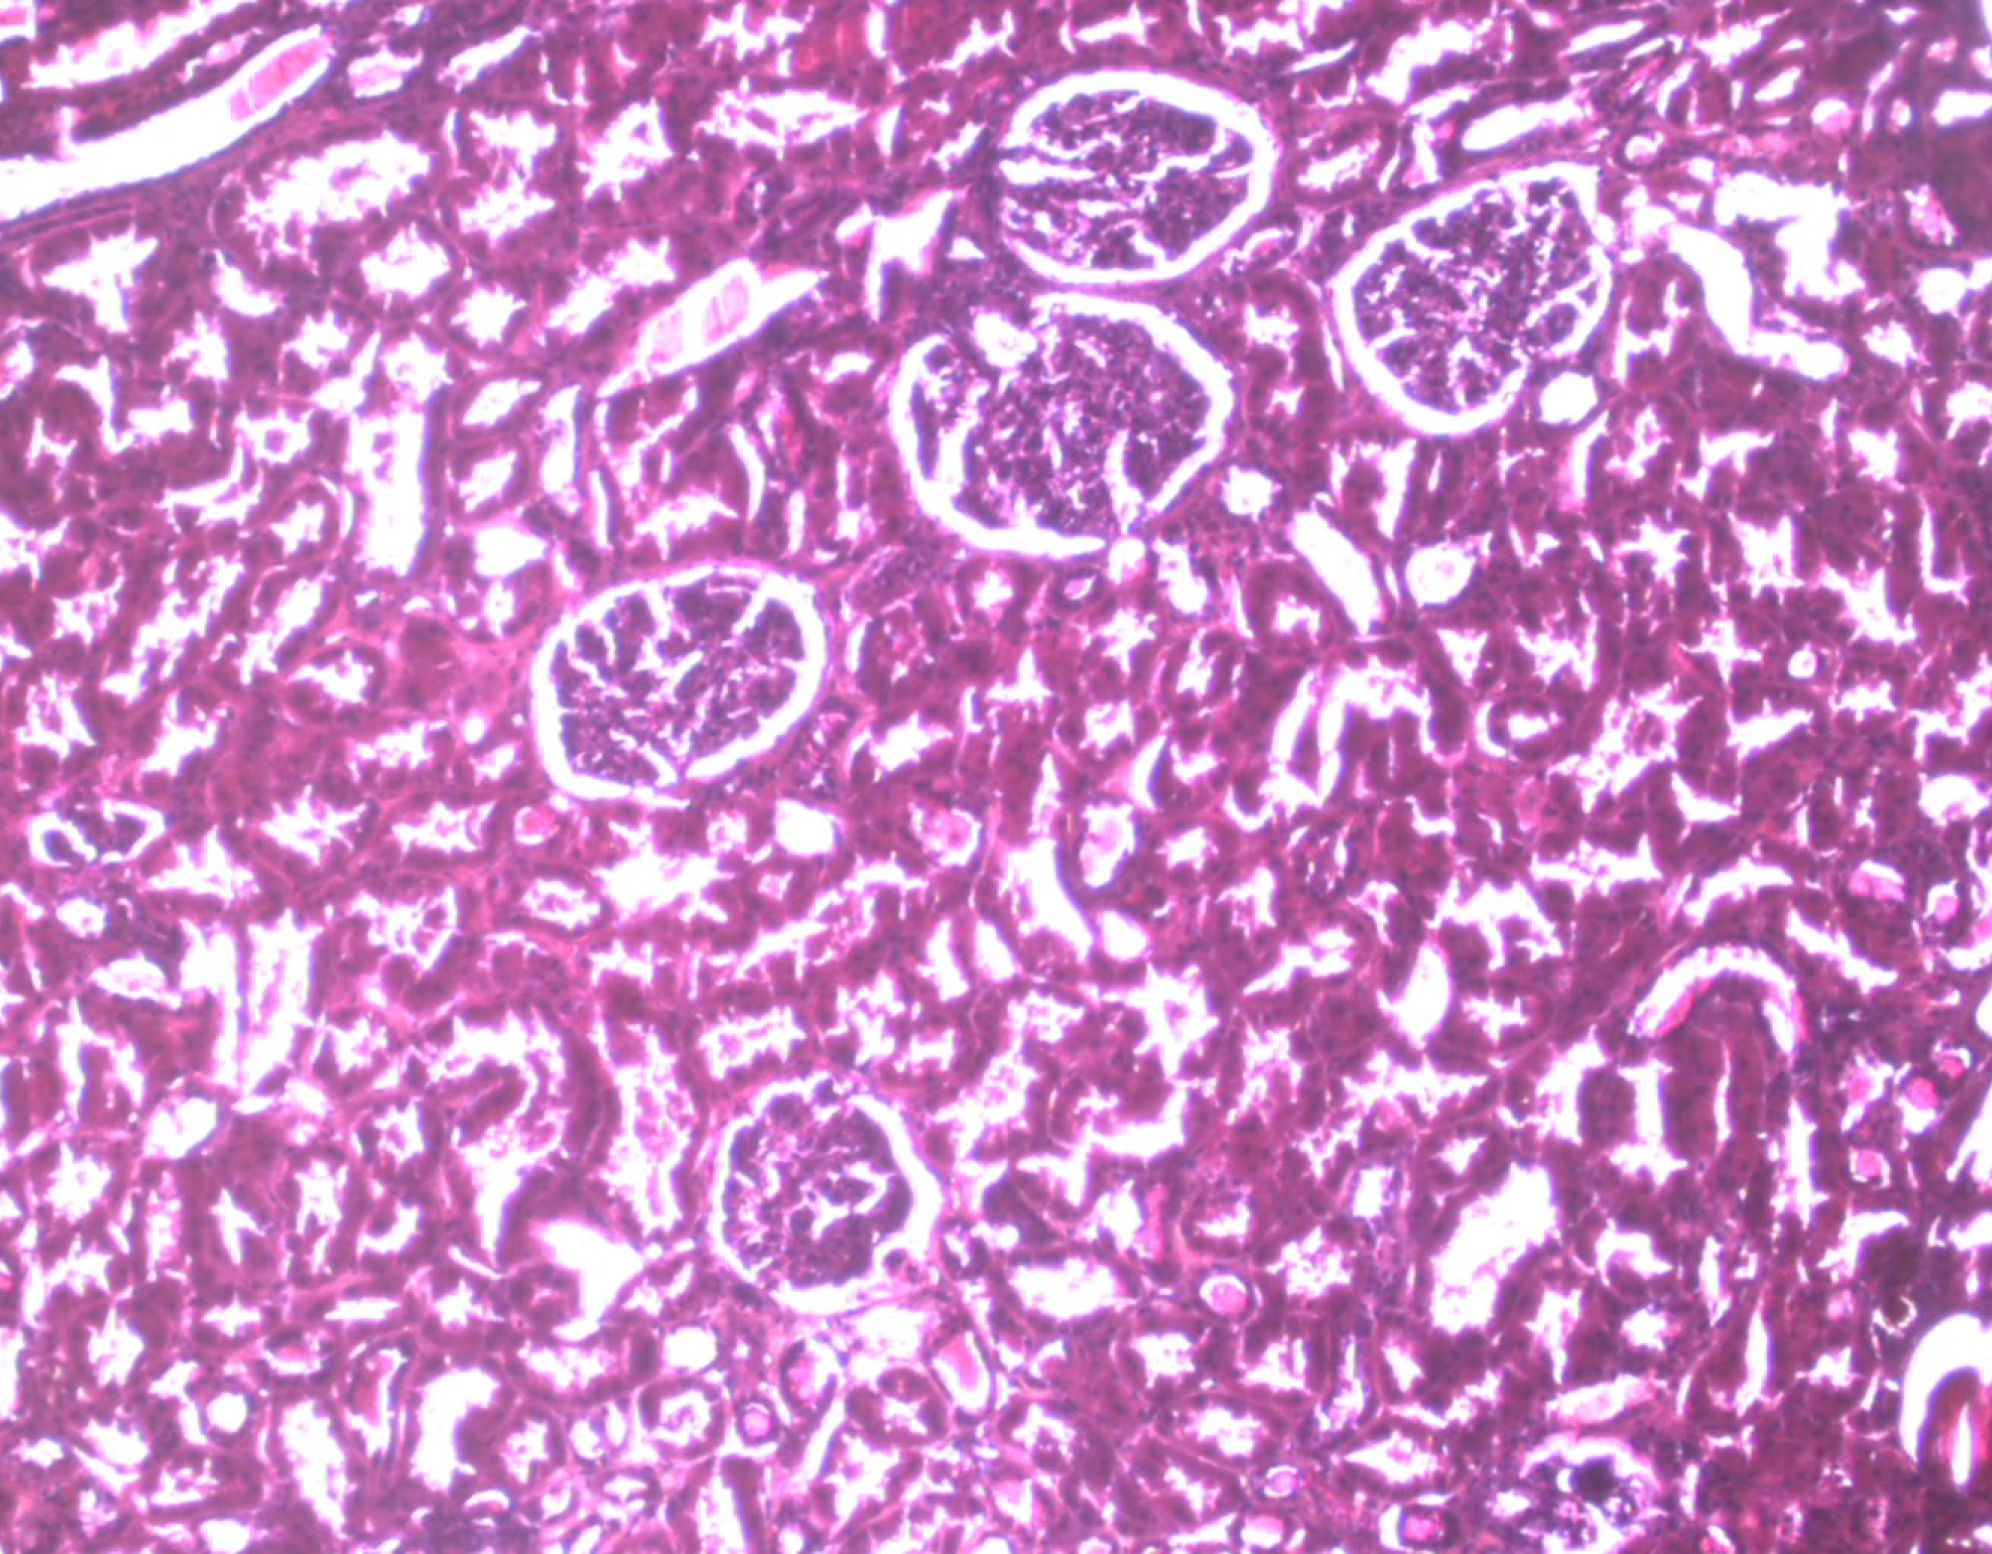

Laboratorul este dotat cu echipamentul necesar pentru tehnicile patologice clasice, cum ar fi fixarea țesuturilor, secționarea în bloc, criosecția, colorarea standard și specială, precum și cu un dispozitiv automat Ventana Benchmark GX care permite colorarea imunohistochimică și hibridizarea in situ.

Tehnicile speciale care pot fi efectuate în laborator includ microdisecții cu captură laser pe lame de țesut încorporate în parafină, țesut proaspăt criosecționat sau celule vii. Laboratorul este, de asemenea, echipat cu microscoape optice clasice, microscoape multitete care permit vizualizarea simultană a materialului histologic, microscoape care permit examinarea în lumină polarizată, câmp întunecat și fluorescență.

Această combinație de tehnici clasice și speciale de anatomie patologică este optimă pentru realizarea protocoalelor de cercetare care implică prelevarea de probe, fixarea și utilizarea de material biologic uman sau animal.